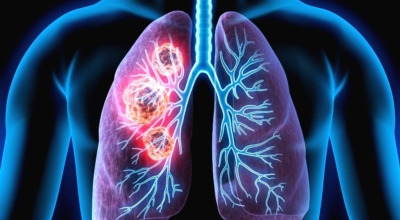

최근 슈퍼푸드로 주목받고 있는 적양파는 알리신 성분이 풍부한데요, 이 성분은 항염, 항균, 항산화 효과가 뛰어나 폐 건강에 좋은 채소입니다. 양파에 들어있는 퀘르세틴 성분도 항산화 작용을 하며 세포 손상을 예방해 폐에 생길 수 있는 염증이나 폐암을 미리 막아줍니다.

케일은 여러 매체에서 체중 감량에 효과적인 음식으로 잘 알려져 있죠. 페놀과 플라보노이드라는 성분이 폐암 예방에 큰 도움이 됩니다. 다른 채소들에 비해 유해 물질을 미리 차단하는 역할이 뛰어나 흡연자가 있다면 케일을 갈아 자주 마시는 것이 좋습니다. 쓴맛이 강해 케일만 갈아 먹기 힘들다면 사과 같은 맑은 즙이 나는 과일과 함께 갈아 드시면 훨씬 마시기 편합니다.

비트에는 매우 풍부한 항산화 성분이 함유되어 있습니다. 마그네슘, 칼륨, 비타민 C, 카로티노이드 같은 산화 억제 성분들은 폐의 염증을 완화하는 데 효과적이며, 천식, 기침, 폐렴 예방에도 도움을 줍니다. 특히 비트에 풍부하게 들어 있는 ‘베타인’이라는 성분은 암세포를 사멸시키는 역할을 하는데요, 한 연구에 따르면 베타인을 많이 섭취한 그룹의 폐암 발병률이 30% 이상 낮아지는 것으로 나타났습니다.